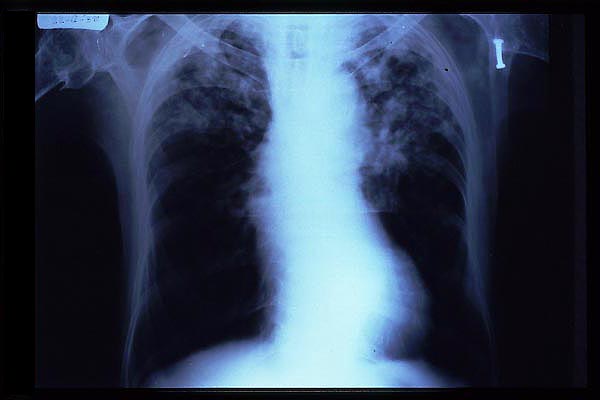

TBC pulmonar antigua